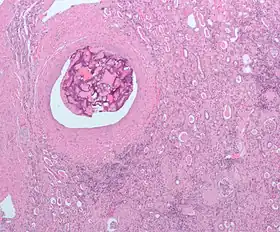

| Micrograph of embolic material in the artery of a kidney. The kidney was surgically removed because of cancer. H&E stain. | |